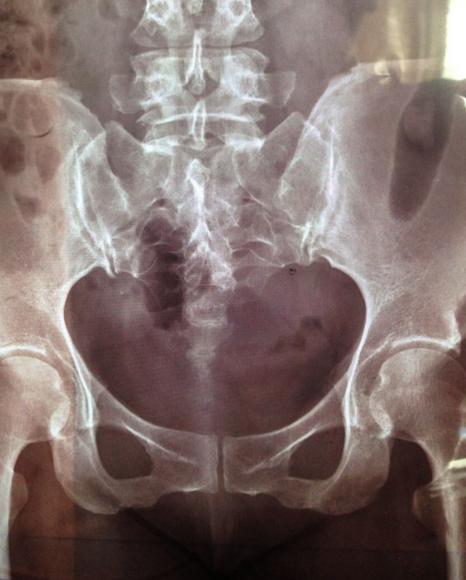

尾椎骨是人类从灵长类进化的证据之一,在脊椎结构上属于最末端,不具支撑或保护脏器的功能,是尾巴退化之后残留一小段的骨性结构。女性的尾骨较男性长且直,由于这男女生理构造上的差异,女性因跌坐造成尾骨受伤的机率较男性为高。另外,女性在分娩时也可能因为胎儿经过产道时造成尾骨压迫而挫伤。

尾骨疼痛基本上多以保守治疗为主,即便是尾骨骨折骨折也仅有极少数患者须以手术治疗。保守性的治疗包括电疗、超声波、冷激光、徒手复位、复健运动等等,或直接以类固醇,止痛药剂直接注射于荐椎尾骨。

尾骨周边有许多骨盆腔的肌肉与韧带,因此若单单只针对尾椎治疗而不加以矫正骨盆周边因疼痛而不平衡的肌群或韧带,治疗效果将是事倍功半。因此维持骨盆的整体平衡是相当重要的一环。